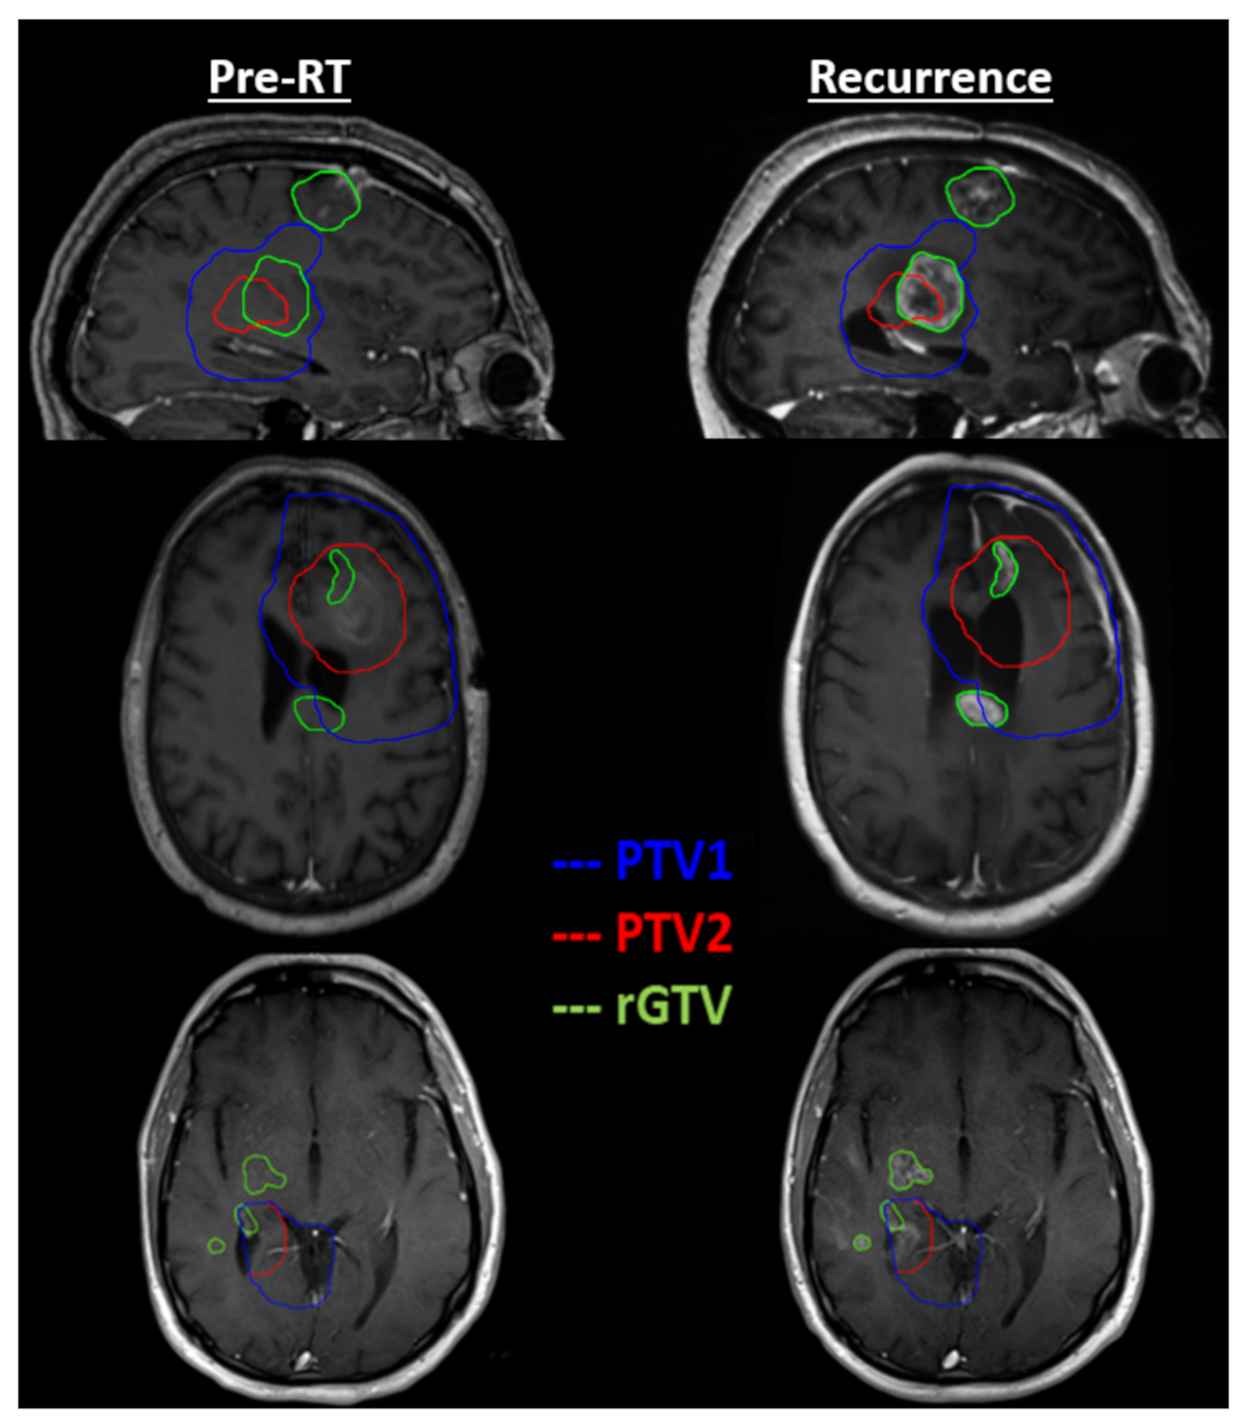

| Study ID | Minimum Dose (Gy) | Maximum Dose (Gy) | Mean Dose (Gy) | rGTV Overlap with PTV1 | rGTV Overlap with PTV2 |

|---|---|---|---|---|---|

| Cohort 1 | |||||

| QINU01EM001 | 59.0 | 65.2 | 62.3 | 100.0% | 100.0% |

| QINU01EM002 | 61.1 | 63.4 | 62.4 | 100.0% | 100.0% |

| QINU01EM003 | 59.4 | 63.8 | 61.8 | 100.0% | 100.0% |

| QINU01EM004 | 61.9 | 64.5 | 63.1 | 100.0% | 100.0% |

| QINU01EM005 | 60.3 | 63.5 | 62.5 | 100.0% | 100.0% |

| QINU01EM006 | 61.1 | 64.2 | 62.5 | 100.0% | 100.0% |

| QINU01EM007 | 60.2 | 63.6 | 62.0 | 100.0% | 100.0% |

| QINU01EM008 | 11.8 | 64.7 | 58.7 | 90.9% | 69.9% |

| QINU01EM010 | 52.2 | 64.7 | 62.3 | 100.0% | 99.1% |

| QINU01EM011 | 44.1 | 64.7 | 62.2 | 99.8% | 99.5% |

| QINU01EM012 | 58.7 | 63.6 | 61.9 | 100.0% | 94.5% |

| QINU01EM013 | 59.0 | 64.1 | 61.8 | 100.0% | 100.0% |

| QINU01JH001 | 60.1 | 63.2 | 61.4 | 100.0% | 99.8% |

| Cohort 2 | |||||

| QINU01EM014 | 52.2 | 63.2 | 58.2 | 100.0% | 50.1% |

| QINU01EM015 | 58.7 | 62.8 | 61.2 | 100.0% | 96.2% |

| QINU01EM016 | 56.2 | 64.9 | 62.8 | 99.2% | 99.2% |

| QINU01EM017 | 10.9 | 50.3 | 25.2 | 0.0% | 0.0% |

| QINU01EM019 | 60.2 | 63.2 | 61.6 | 100.0% | 100.0% |

| QINU01EM021 | * | * | * | * | * |

| QINU01EM022 | 59.6 | 62.8 | 61.0 | 100.0% | 100.0% |

| QINU01EM023 | 45.6 | 53.4 | 50.3 | 0.0% | 0.0% |

| QINU01EM024 | 59.5 | 63.8 | 61.6 | 100.0% | 100.0% |

| QINU01JH002 | 60.0 | 62.1 | 61.0 | 100.0% | 100.0% |

| QINU01JH003 | 1.9 | 63.8 | 32.3 | 13.4% | 13.4% |

| QINU01EM025 | 19.8 | 21.7 | 20.9 | 100.0% | 100.0% |

| QINU01EM026 | * | * | * | * | * |